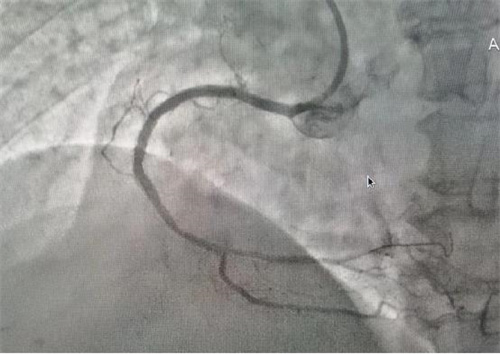

術(shù)中

4月23日,湖南省寧遠(yuǎn)縣中醫(yī)醫(yī)院心病科在郴州市湘南學(xué)院附屬醫(yī)院心血管內(nèi)二科李維軍主任的指導(dǎo)下,順利完成了冠脈造影+經(jīng)皮冠狀動脈內(nèi)支架植入術(shù),該項技術(shù)的開展標(biāo)志著醫(yī)院心臟介入診療技術(shù)開啟了新篇章。

據(jù)了解,此次順利完成經(jīng)皮冠狀動脈內(nèi)支架植入術(shù)的患者共有4位,其中一名68歲老年女性患者,因胸悶氣促6余年,活動后明顯加重入院治療。經(jīng)冠脈造影檢查,發(fā)現(xiàn)左前降支次全閉塞、右冠99%重度狹窄,三支血管重度病變,情況危急。經(jīng)病情評估后,與患者家屬溝通,決定立即對右冠實施冠狀動脈球囊擴張加支架植入術(shù)。在上級專家的指導(dǎo)下,心病科團隊成功擴張了狹窄血管、植入支架,手術(shù)順利,患者術(shù)后安返病房,為患者后續(xù)治療創(chuàng)造了有力條件。